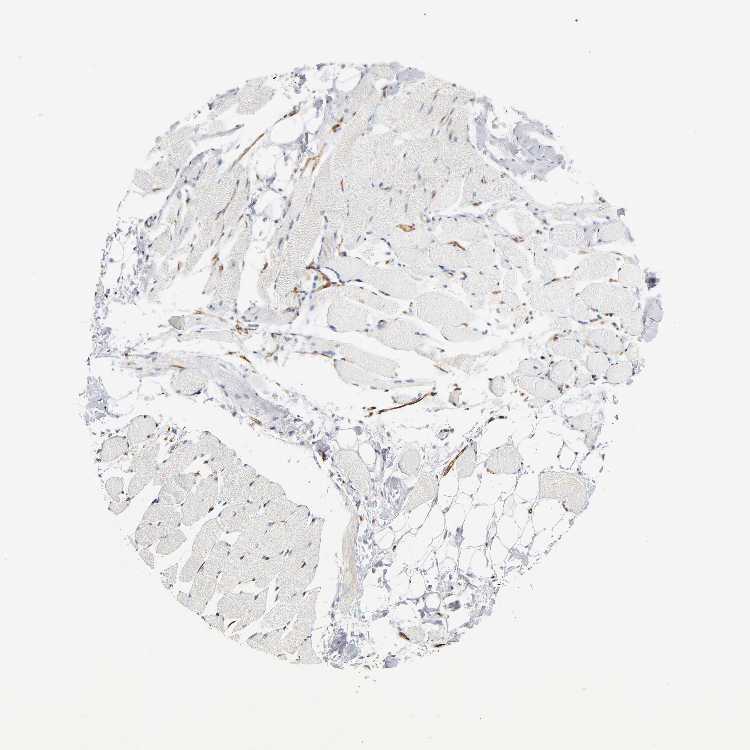

SKELETAL MUSCLE - Antibody stainingi

Antibody staining in the annotated cell types in the current human tissue is reported as not detected, low, medium, or high, based on conventional immunohistochemistry profiling in selected tissues. This score is based on the combination of the staining intensity and fraction of stained cells.

Each image is clickable and will lead to virtual microscopy that enables deeper exploration of all samples and also displays staining intensity scores, fraction scores and subcellular localization as well as patient and tissue information for each sample.

Antibody HPA002126Antibody HPA004877Antibody CAB002142

Myocytes Not detectedNot detectedNot detected